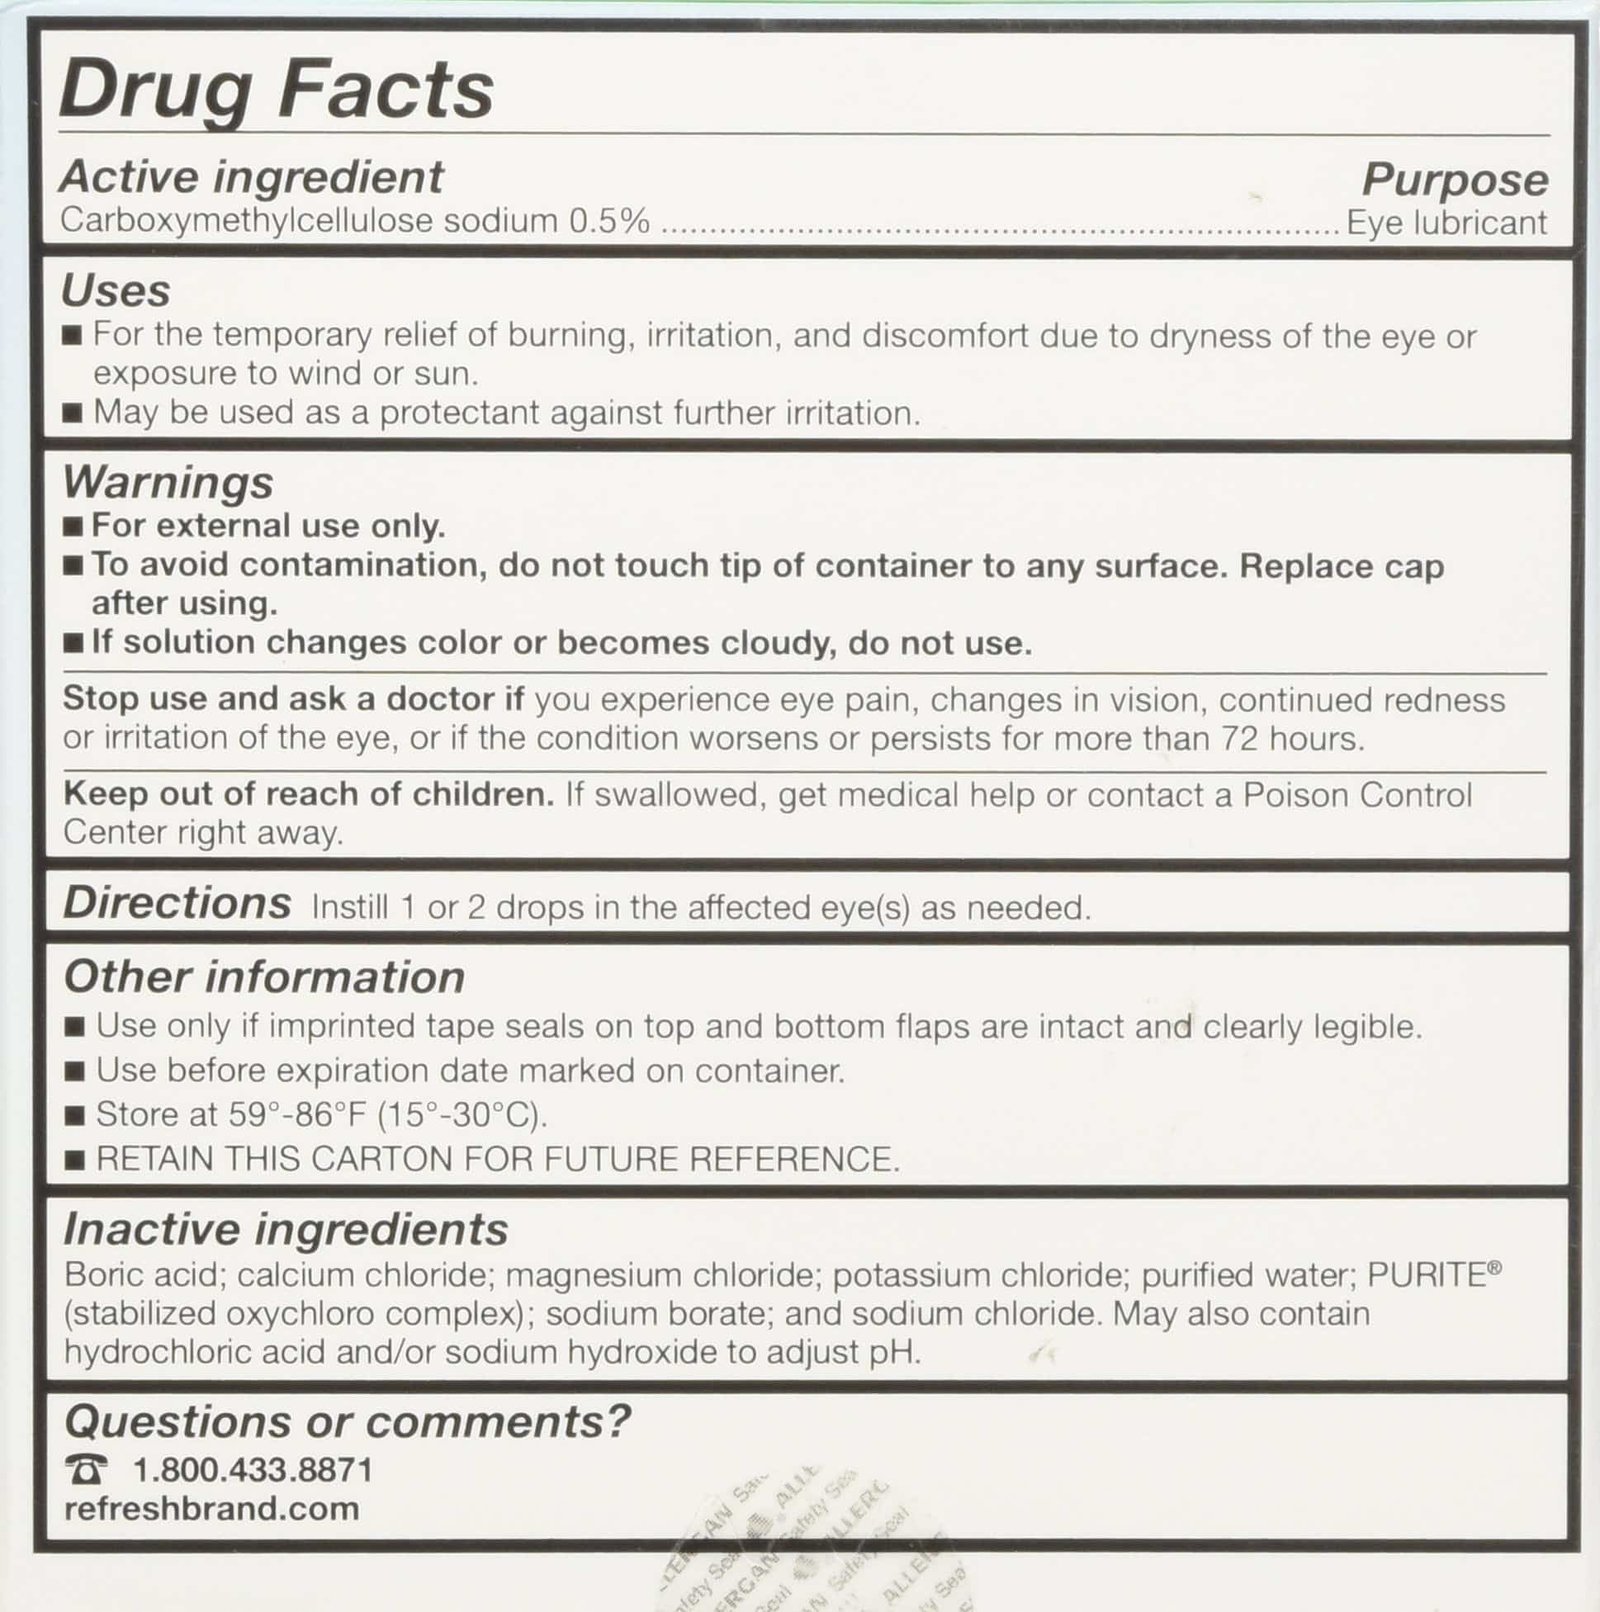

Original price was: ₹14,184.₹10,507Current price is: ₹10,507.Refresh Multi-Pack 65 ml Refresh Tears, 2.17 FlOZ

2.17 fl oz. Refresh Tears Lubricant Eye Drops, Moisture Drops for Dry Eyes. 4- .5 fl oz. bottles and 1- .17 fl oz bottle